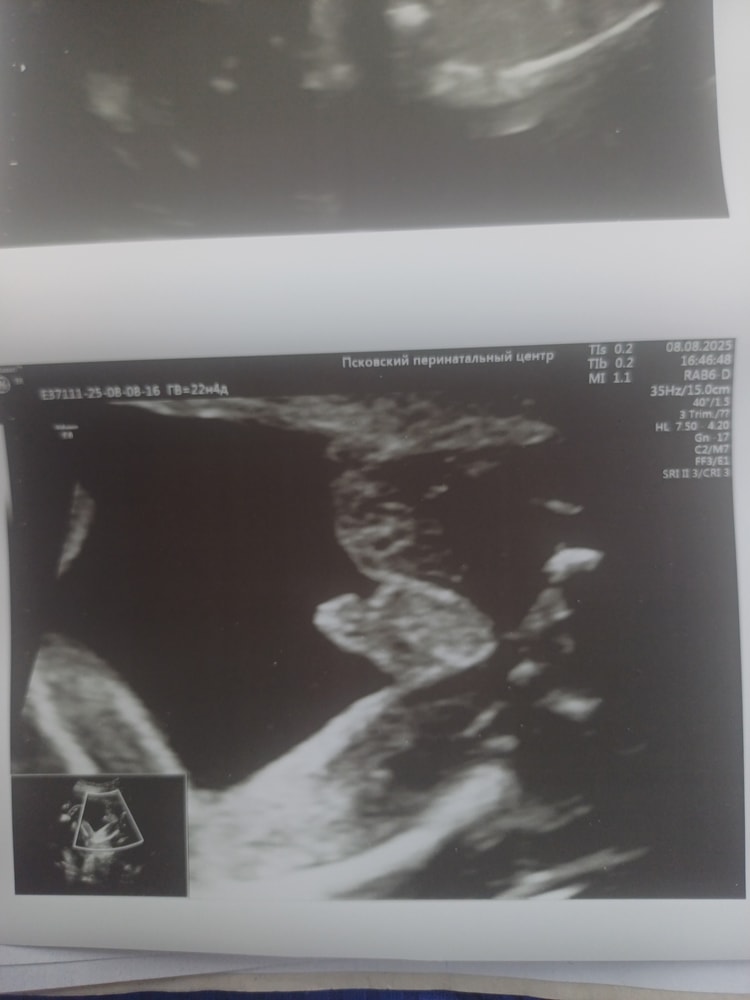

УЗИ, КТГ, доплерПоказала значит я фотки с узи своим подружкам мол ждем мальчика,а они мне начали говорить,что похоже на девочку больше.Либо с беременностью я стала более внушаемой,но теперь сомневаться начала и мой беременный мозг уже сносит🥲Врач четко показала на узи между ног,что есть 🔔🔔 и я четко видела.Еще раз приложу фотки узи,обвела что врач имела ввиду.Это ракурс как раз между ножек.Сказала у девочки не может так за контуры тела выходить.Короче,девочки кто разбирается в узи успокойте меня и мое любопытство.Хотели уже родных собирать пока тепло сообщать о внуке,а теперь во мне сомнение затесалось.Ну мальчик же,нет?Умоляю,не пишите про сдачу крови только.Если бы я знала,что так долго надо будет ждать и терпеть,то сдала бы уже на 10 неделе и не мучилась(